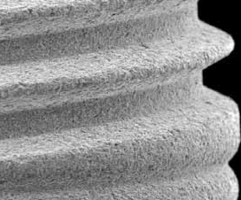

Titanul de grad 23 (Ti 6Al 4V ELI) este un material de mare succes pentru fabricarea implanturilor dentare, datorită combinației favorabile a proprietăților sale, cum ar fi greutatea netă scăzută, raportul înaltă rezistență la greutate, modulul de elasticitate ridicat, coroziunea foarte ridicată rezistență și o bună biocompatibilitate generală.

Capacitatea excelentă de biocompatibilitate și osseointegrare a titanului este legată de proprietățile materialului și de suprafața acestuia:

– O peliculă de oxid pasiv rezistent, foarte rezistent, care protejează metalul substrat de oxidare și coroziune.

– O rată de dizolvare foarte scăzută a filmului de oxid și o concentrație extrem de scăzută a titanului încărcat.